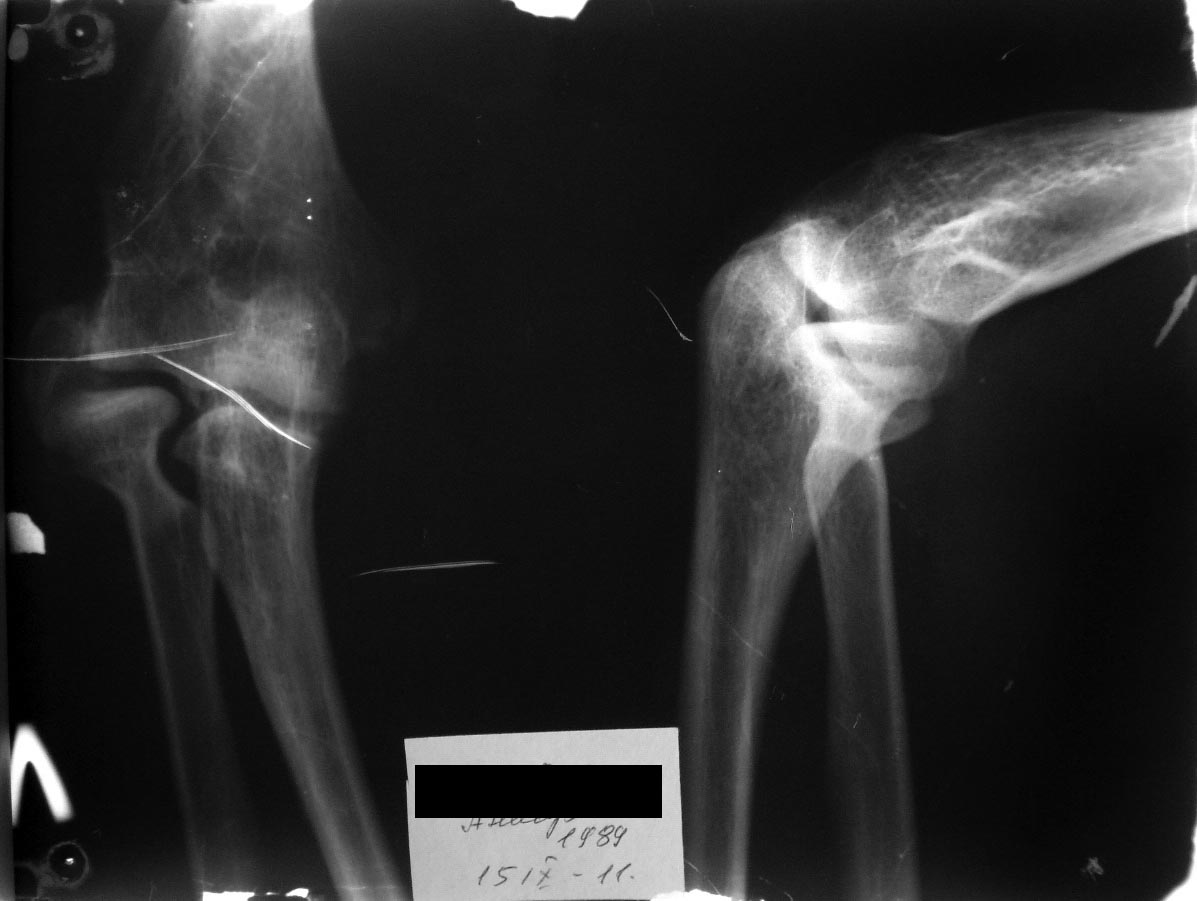

Перелом латерального надмыщелка плеча. Какова тактика?

Молодой человек, 21 год. Перелом латерального надмыщелка 7 лет назад. Лечили консервативно, гипсовая иммобилизация без должного контроля.

В настоящий момент беспокоит ограничение амплитуды движений в локтевом суставе, деформация локтевого сустава (за счет смещенного фрагмента). Есть ли смысл браться за скальпель и долото? Беспокоит вопрос насколько улучшится функция локтевого сустава? Думаю отделить фрагмент и поставить его на место, фиксировав двумя винтами ( 1 в блок, 2ой в латеральную колонну). Также беспокоит вопрос латеральной боковой связки, даст ли она поставить все на место... Буду рад услышать мнение коллег по этому поводу...

это сместившийся фрагмент головчатого возвышения.

Рекомендую сделать задний латеральный разрез и удалить этот фрагмент. Нестабильности не будет